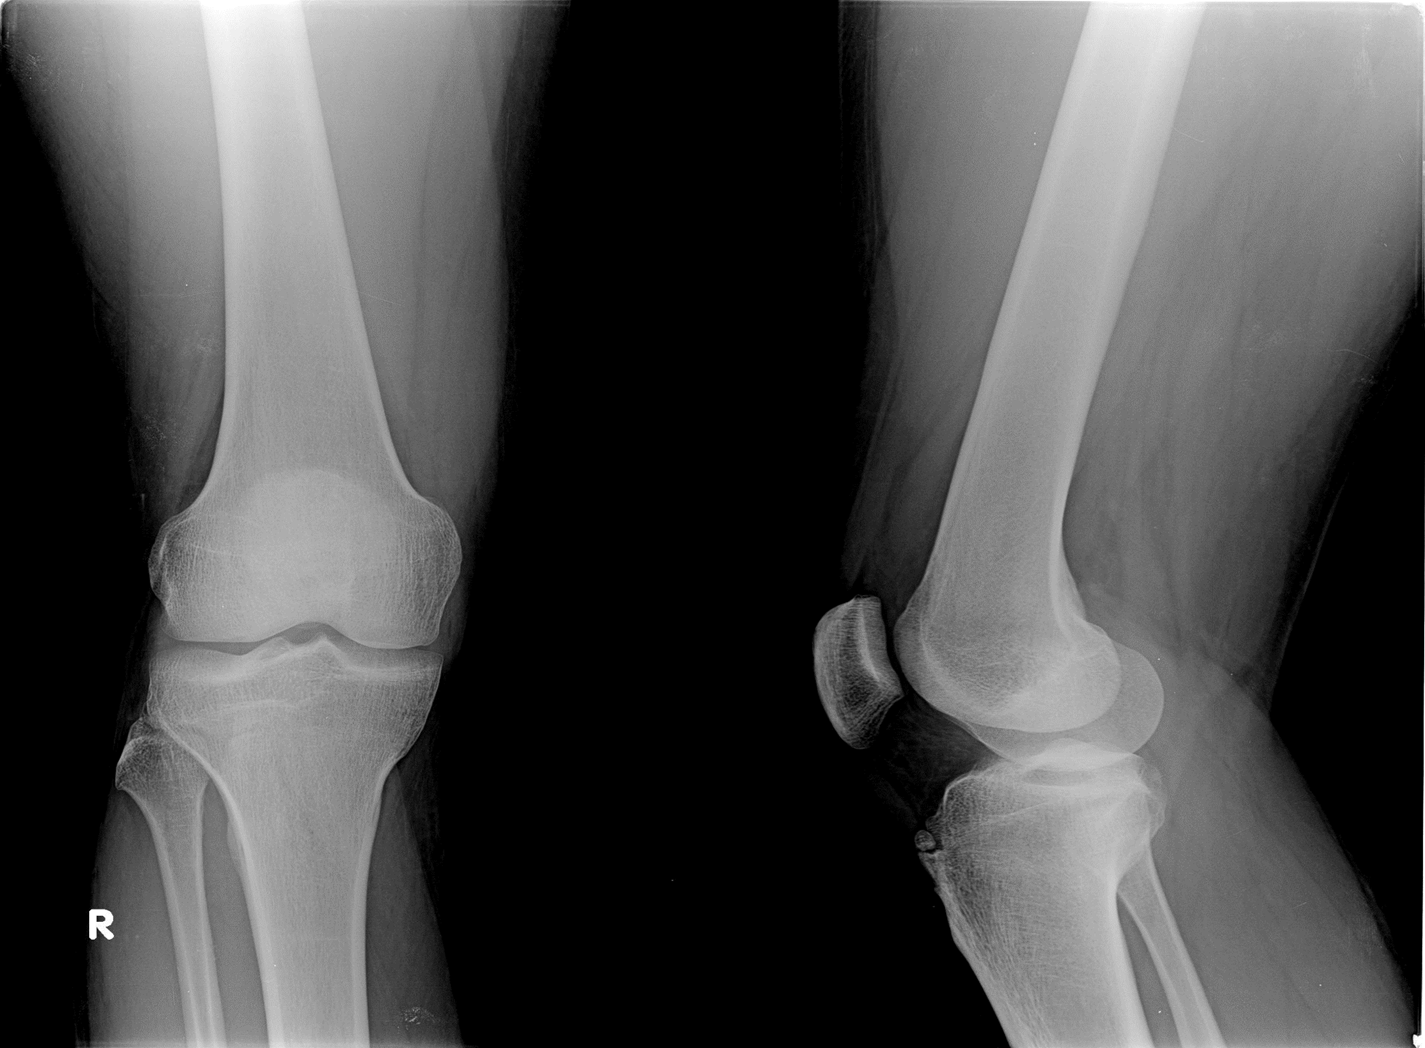

Osteoarthritis

(Degenerative Joint Disease)

Generalized disorder pathologically characterized by loss of joint cartilage and reactive new bone formation.

Cause: traumatic, stress to joints

Complications: joint pain, stiffness, trouble using joints for walking, grasping, etc

Radiographic Appearance: irregular narrowing of joint spaces and development of small bony spurs (osteophytes)

•Knee – articular ends become increasingly dense and joint narrowing is asymmetric

•Fingers – affect distal joints, marginal spurs produce well defined bony protuberances (can palpate and see knobby appearance)

•Hip – asymmetric narrowing of joint space (superiorly and laterally)

Technical: Advance Stage – Subtractive disease

•May require slight decrease

Prognosis: Some patients are unaffected by osteoarthritis while others can be severely disabled.

•Joint replacement surgery for some results in the best long-term outcome.